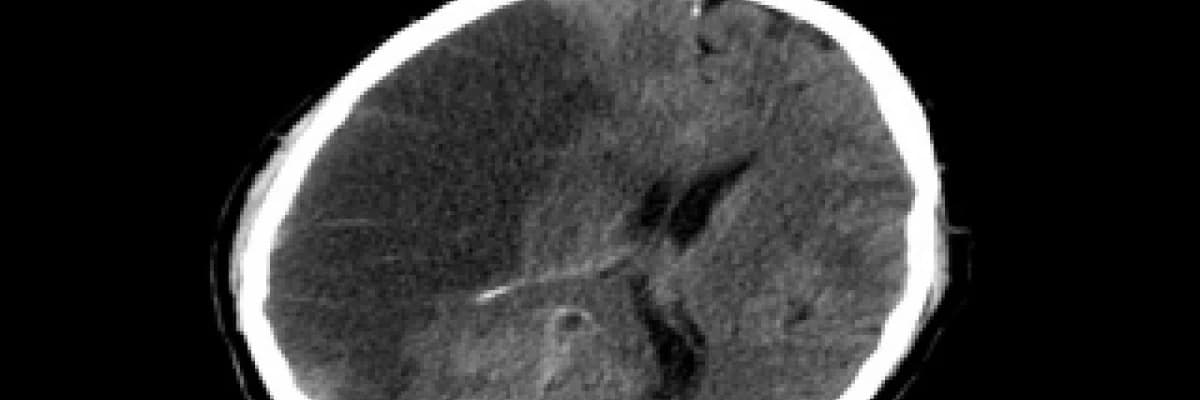

NÖROLOJİK CHECK UP... FELÇ İÇİN TEDBİR ALIN

NÖROLOJİK ERKEN TEŞHİS İÇİN FELCİ RİSKİNİ AZALTMAK İÇİN NELER YAPILIR :

Beyin MR MRAngio ve MRVenografi